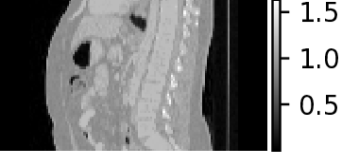

| Density map (g/cc) | Organ dose map (mGy) | |

Axial |

![]() |

|

Sagittal |

Coronal |

For individualized patient organ dose, patient CT images were used to generate patient-specific voxelized phantoms that contain spatial maps of both material type and mass density. The CT images were first resampled to isotropic voxels of mm3 to keep the computational demands reasonable. The density mapping was performed following a piece-wise linear curve which defines the densities of the mixture of water and bone [45]. Figure 5 visualizes the MC-GPU inputs of mass density and corresponding material map in different views (axial, sagittal, coronal) of a patient CT scan.

We simulated a helical scan from the most superior to most inferior slice for the geometry of a GE Revolution CT scanner. Table 1 lists the modified set of parameters for our MC-GPU configuration. We repeated the MC-GPU dose simulation with uniformly spaced apart start angles . Considering the actual start angles cannot be controlled prospectively, therefore, we averaged the dose maps to obtain the dose map [41].

where, is the voxelized phantom and denotes the set of all the parameters used to configure the MC-GPU simulation. MC-GPU dose is reported as eV/g/photon and was scaled to the more standard mGy for a 100 mAs scan with constant tube current, using a scanner-specific calibration to convert a simulated 32 cm CT dose index (CTDI) phantom to a physical CTDI measurement (1 eV/g/photon = 1.8143 mGy/100 mAs). Figure 5 visualizes a representative dose map. Using a threshold g/cc in the voxelized phantom, we masked out the air and obtained the patient body dose map. Therefore, from average dose map in (2), the final dose map is obtained as

An example patient CT density map and the corresponding organ dosemap (segmented organ contours overlaid on the dosemap) at three different views obtained from the modified MC-GPU tool can be seen in Figure 5. Moreover, Figure 6 shows the distributions of organ and patient body doses for all the patient CT scans.